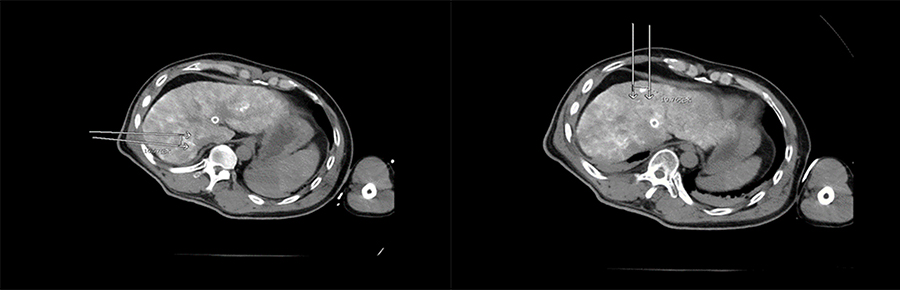

▲ 患者一计划进针路线

▲ 患者二计划进针路线